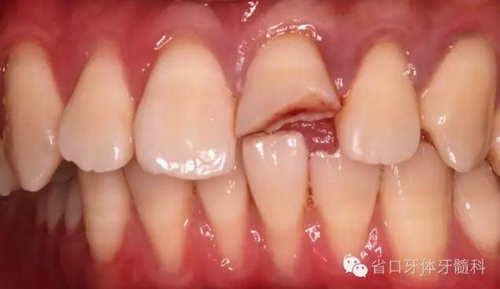

口內(nèi)檢查:21切1/3-1/2折斷,髓腔暴露,探痛明顯

近中鄰面探及齲損,松-,叩+,齦緣輕度紅腫,探及齦下結(jié)石。

術(shù)前口內(nèi)照

斷冠

折斷之牙體嚴(yán)重脫水,呈白堊色,斷端對(duì)位后吻合度較好,僅少許牙體缺損。